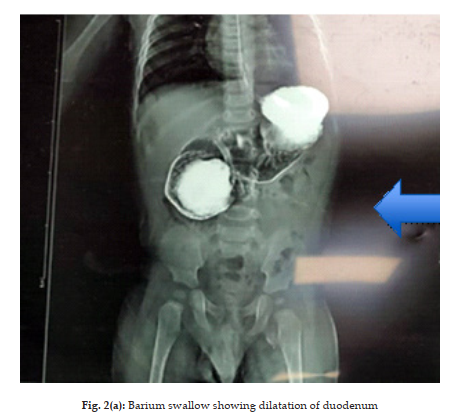

Background: Annular pancreas (AP) is a congenital disorder of the pancreas, thought to result from the malrotation of the ventral pancreatic bud. This causes the duodenum to be encircled by the pancreatic tissue, leading to duodenal obstruction. The management of annular pancreas is usually surgical. Clinical Description: A 10-month-old male infant presented with regurgitation of yellowish feeds for the past few months, with no other positive clinical findings. Radiological investigations revealed an obstruction after the first part of the duodenum. A barium swallow showed duodenal stenosis. The patient underwent surgery, and the diagnosis of annular pancreas was confirmed. Management and Outcome: After clinical and radiological diagnosis, the child was managed surgically and underwent duodenojejunostomy. Postoperatively, the patient remained clinically stable and is symptom-free. Conclusion: Annular pancreas is a rare but significant cause of duodenal obstruction, which can present from the neonatal period to adulthood. The patient may experience bilious or non-bilious vomiting. The definitive diagnosis is made via laparotomy. Surgical management is required, with duodenojejunostomy being the best treatment option.